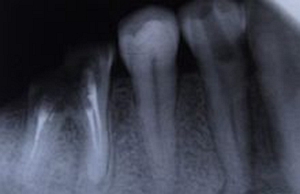

尖周炎癥

由于牙根的牙髓組織發(fā)炎,引起牙根尖組織病變,如根尖牙周膜腔增寬、根尖囊腫等病變均可在牙片上顯示出來。

尖周炎癥作牙片檢查的臨床意義有:

①了解病牙根管情況:如根管數(shù)目、粗細(xì)、彎曲度以及有無鈣化、有無內(nèi)吸收等情況。

②幫助確定病牙:如兩牙之間的瘺管插入牙膠尖作牙片檢查,可以顯示牙膠尖偏于某一牙齒。

③檢查治療情況:如牙片顯示根管充填是否到底或有無超填。